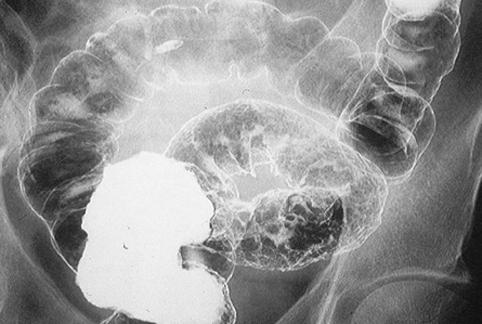

症例提示(所在地,施設名等): 千葉県・ 国立がんセンター東病院

疾患(病理主体)の分類悪性上皮性腫瘍/腺癌

部位(臓器別)大腸/2区域以上の大腸にまたがるもの

検査方法X-P

腫瘍の肉眼分類4型(びまん浸潤型)/

病変の最大径(ミリ)40以上

腫瘍の深達度ss(a1)